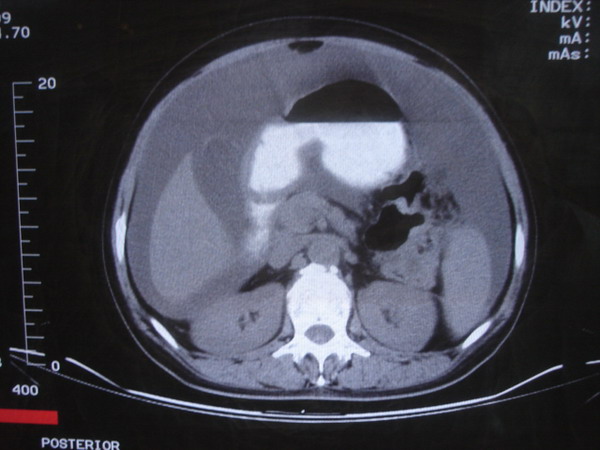

患者 女 52 腹部大量腹水。大家帮忙看看胃窦部有问题吗?

b超显示腹部、盆腔未见异常;化验室检查afp cea 正常,ca125 升高 347.4。

腹部大量腹水。胃窦部胃壁增厚,轮廓不规则!

1)不排除胃癌可能;建议行胃镜检查。2)大量腹水。

网膜不干净,可能为癌性腹膜炎。

腹部大量腹水。胃窦部胃壁增厚,轮廓不规则,胃癌待除外,建议胃镜检查。